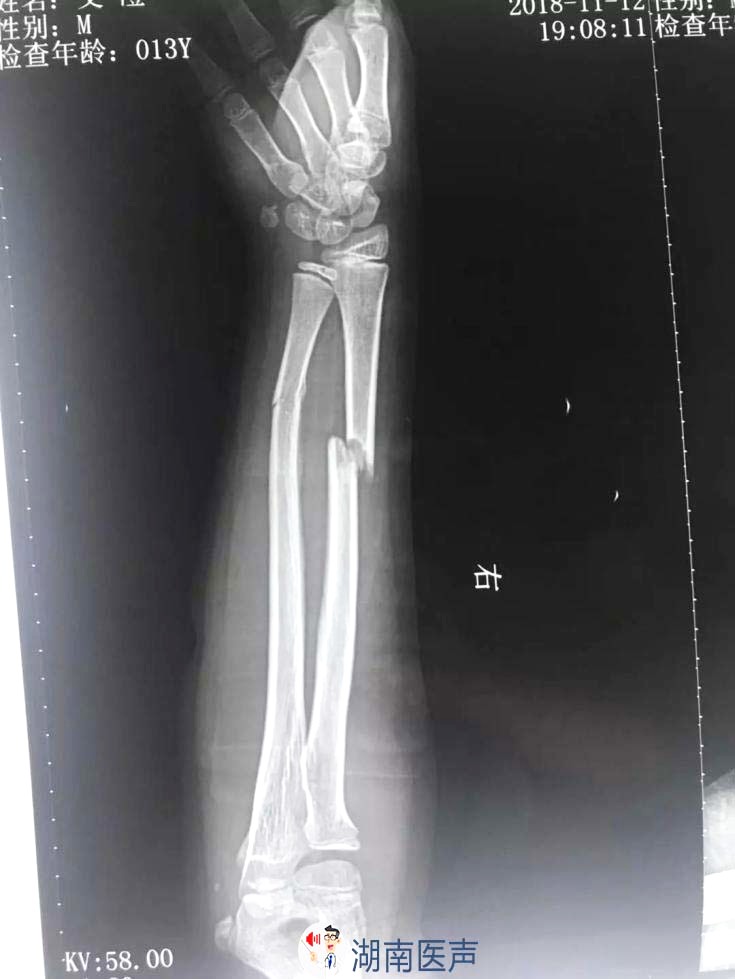

12岁男孩右手臂骨折就医 骨科新技术造福百姓